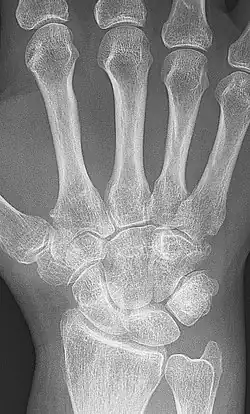

X-ray of the wrist of a woman with rheumatoid arthritis, showing unaffected carpal bones in the left image, and ankylosing fusion of the carpal bones eight years later in the right image

The disease progresses by forming granulation tissue at the edges of the synovial lining, pannus with extensive angiogenesis and enzymes causing tissue damage.[76] The fibroblast-like synoviocytes have a prominent role in these pathogenic processes.[17] The synovium thickens, cartilage and underlying bone disintegrate, and the joint deteriorates, with raised calprotectin levels serving as a biomarker of these events.[77]